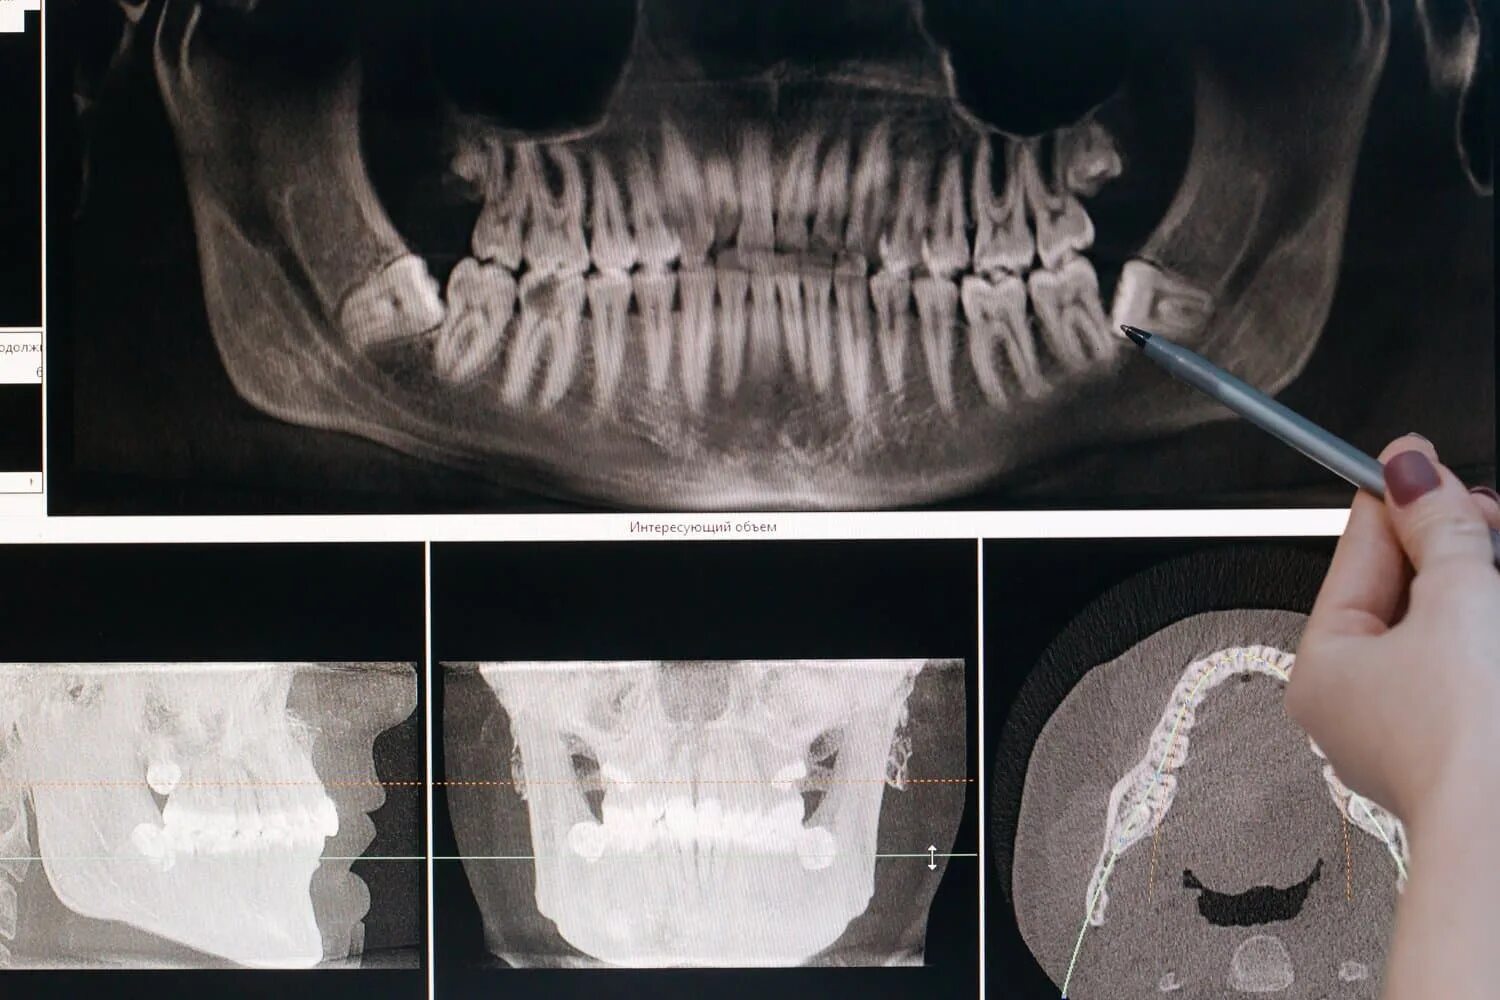

Удаленный зуб 8